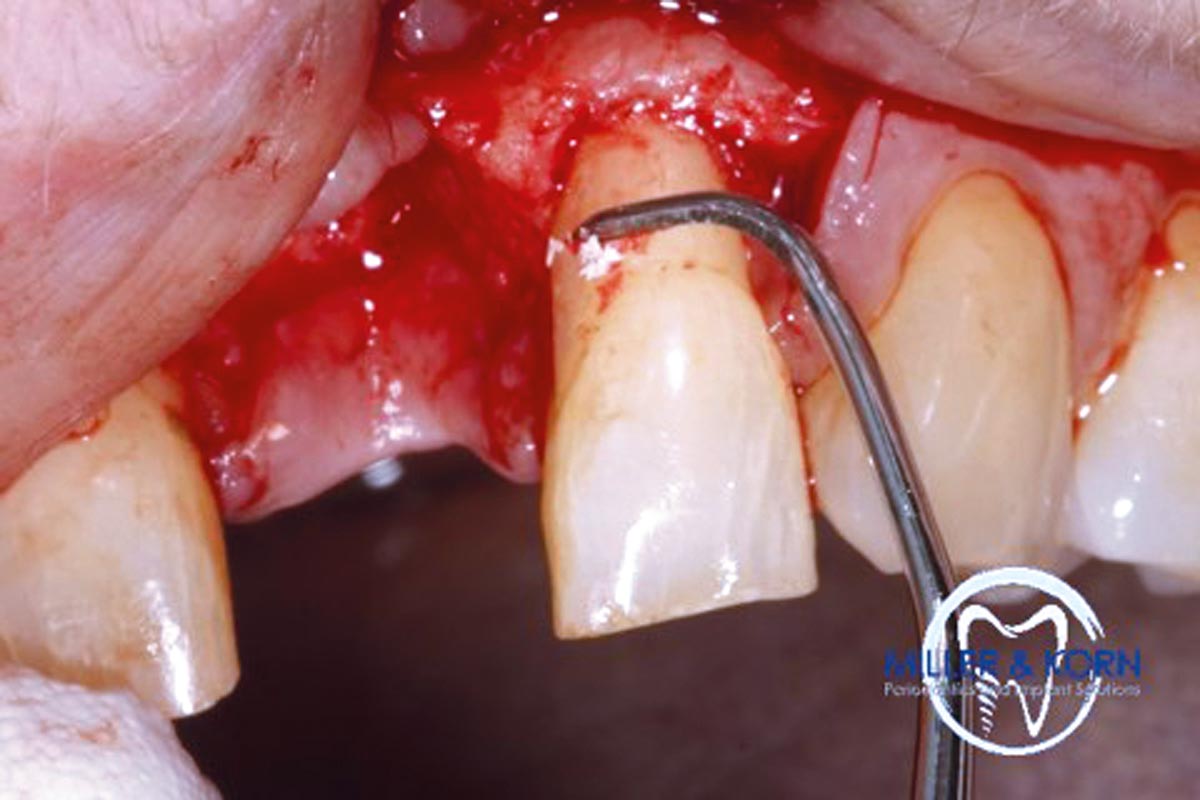

04/39 - Preparation of a full thickness flap and careful debridementImmediate implant placement and correction of horizontal and vertical bone loss using an allograft bone ring, cerabone® and Jason® membrane - Drs. Miller and Korn